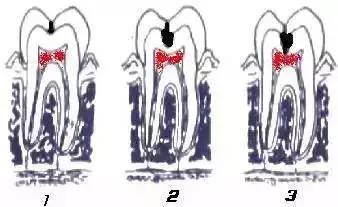

一旦確認牙齒上的小黑點是齲齒就應該儘早修補,以阻止病變的發展。如果任由其繼續發展就會變成明顯的齲洞,這時患者會對冷熱酸甜等食物刺激敏感;當損傷進一步到達牙髓(即老百姓說的「牙神經」),就會疼痛難忍,嚴重影響日常生活。臨床上見到很多人都會等到牙痛得受不了,才到醫院就診。這時通常不能靠單純補牙來解決問題,可能還要做根管治療甚至拔除患牙、進行假牙修復,費時費力又費錢,人還遭罪,可謂「小洞不補,大洞吃苦」。